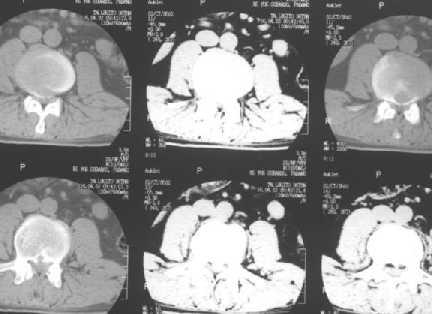

L4-5 Intervertebral disc herniation : with L3 spinal cord tumor